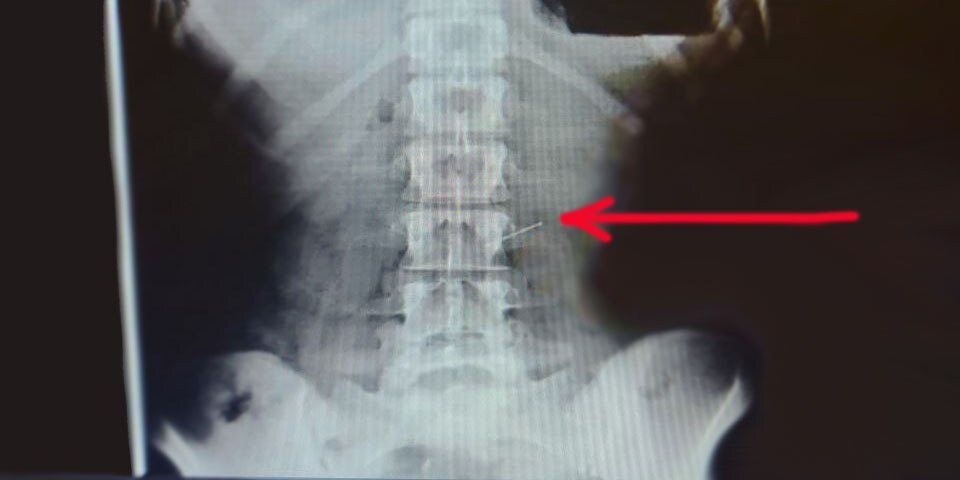

«Поэтому, если вы проглотили иглу, нужно как можно меньше менять положение тела, чтобы предотвратить ее перемещение, - говорит Дмитрий Валерьевич. - Категорически противопоказаны любые резкие движения и наклоны, приём пищи и жидкости. Лучше всего аккуратно лечь на левый бок и в таком положении дожидаться приезда врачей. Наша пациентка так и поступила. В приёмном отделении была выполнена серия обзорных рентгенограмм грудной клетки и живота, на одной из которых удалось визуализировать булавку, располагавшуюся в желудке по большой кривизне и по счастливой случайности она не воткнулась во время движения в мягкие ткани пищевода и глотки».